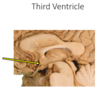

What connects the third and fourth ventricles?

A. Central canal

B. Cerebral aqueduct

C. Interventricular foramen

D. Lateral aperture

E. Median aperture

Answer to flip side Question:

B.

Cerebral aqueduct